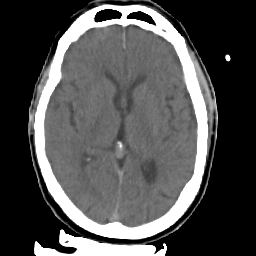

Meningioma: Roentgen-ray CT #2 -- Slice #10

[Home][Help][Clinical] Slice 10